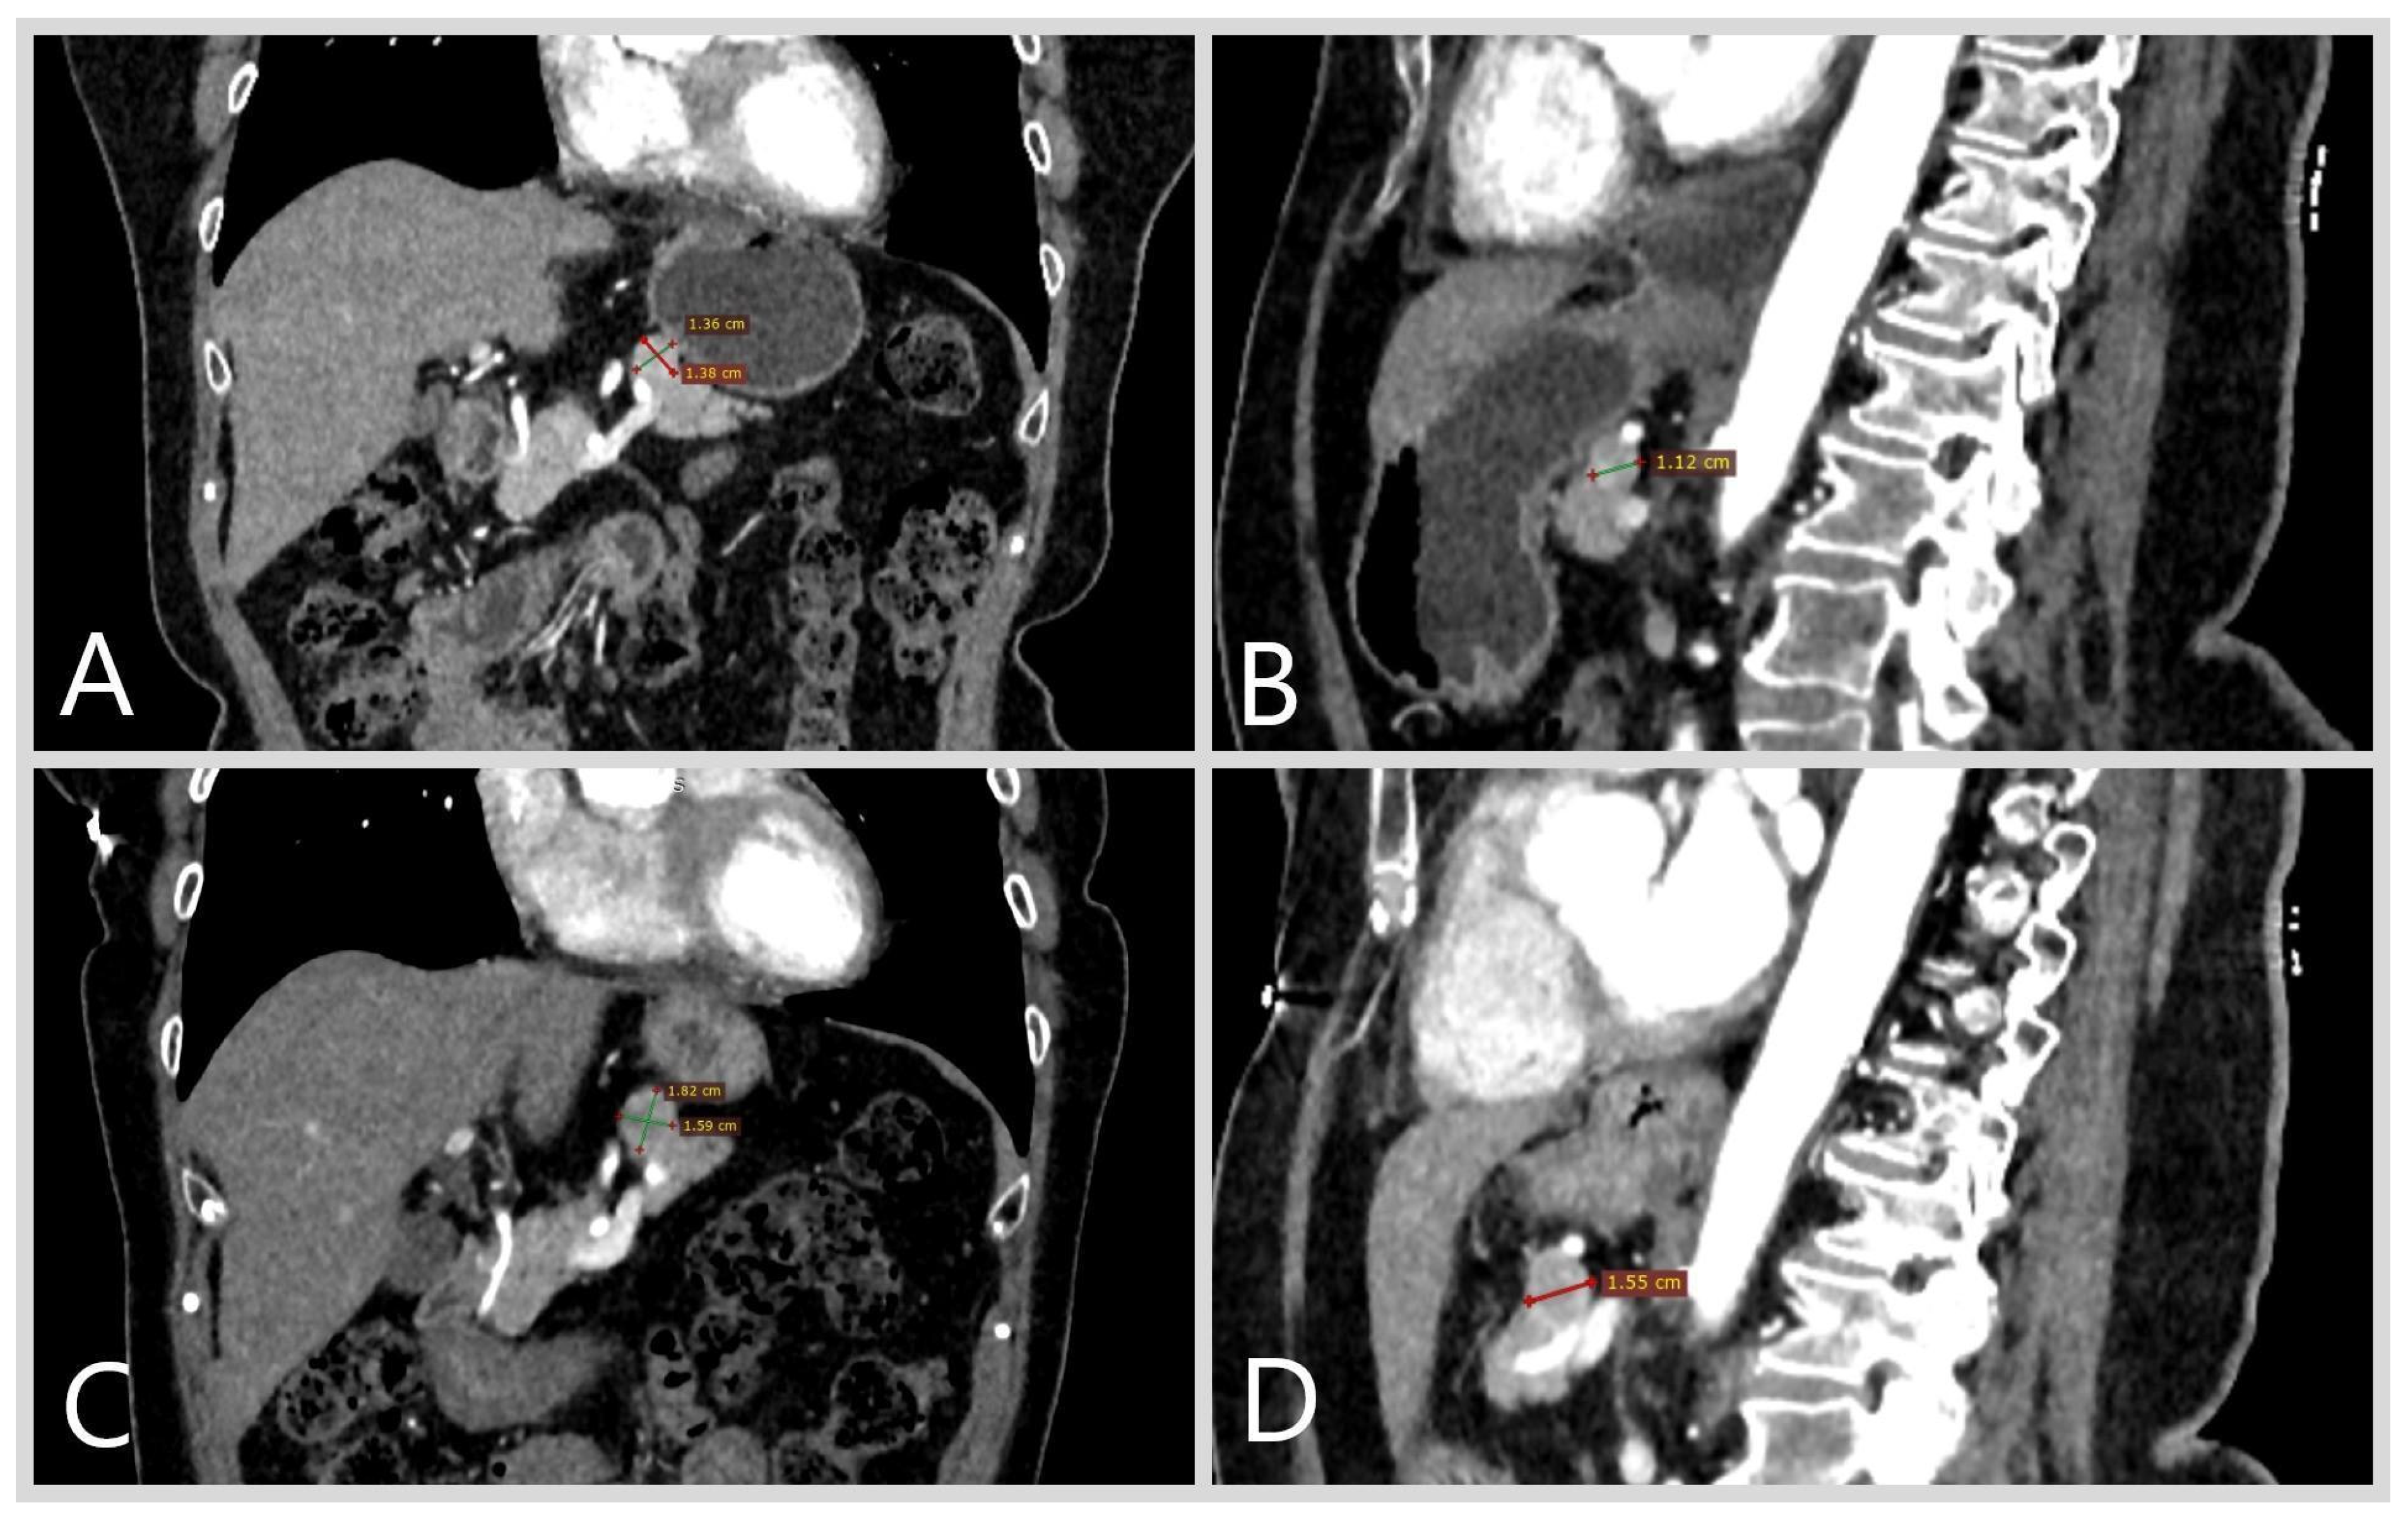

Patient D., female, aged 66 years, presented with discomfort in the epigastric area since December 2021. Upon examination at a local outpatient facility, erosive gastritis was revealed through gastroscopy. Additionally, an ultrasound of the abdominal cavity indicated the presence of a pancreatic tumor 12 × 10 mm in size. Multispiral computed tomography (MSCT), conducted in February 2022, confirmed the presence of pancreatic neoplasm up to 13 mm (Figure 1A,B). Follow-up MSCT with IV contrast enhancement in April 2022 demonstrated a pancreatic tumor of 13 × 12 mm, with a CT pattern consistent with a neuroendocrine tumor. The patient was subsequently referred to a gastroenterologist and surgeon at an expert-level institution.

Figure 1.

Multispiral computed tomography of the abdominal cavity, patient D. The neuroendocrine tumor of the pancreas body, with the indicated size, is highlighted with arrows. Frontal (A) and sagittal (B) views of the MSCT performed in February 2022. Frontal (C) and sagittal (D) of the MSCT performed in August 2023.

The patient was diagnosed with a nonfunctional NET of the pancreatic body. The diagnosed comorbidities included grade 1, stage 1 arterial hypertension, chronic superficial gastritis, and hiatal hernia. Considering the absence of hormonal activity, small size, and lack of tumor growth over time, surveillance at a specialized expert center (every 6 months) was recommended to the patient. Follow-up MSCT in August 2023 demonstrated tumor growth, reaching a size up to 18.3 × 15 mm (Figure 1C,D).